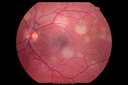

OD: Vertical C/D ratio is 0.2. There is no posterior vitreous separation and 1+ vitreous cells. There are some splotchy white geographic areas in the posterior pole.

OS: Vertical C/D ratio is 0.2. There is no posterior vitreous separation. There are 1+ vitreous cells. Again, there are splotchy white geographic areas in the posterior pole. In neither eye do the white spots involve the center of the macula.

Acute Posterior Multifocal Placoid Pigment Epitheliopathy - APMPPE - Fundus Photo - Color1602 views 25-year-old man with one and half weeks ago he woke up with night chills. Also around that time his joints started hurting him. He also has headaches, although the headache at this point is not severe. His vision has been changing for about the last week and a half. He sees some spots in his vision and they are blurred spots. They are not in the central vision.

VISUAL ACUITY: OD 20/32, OS 20/32     (0 votes)